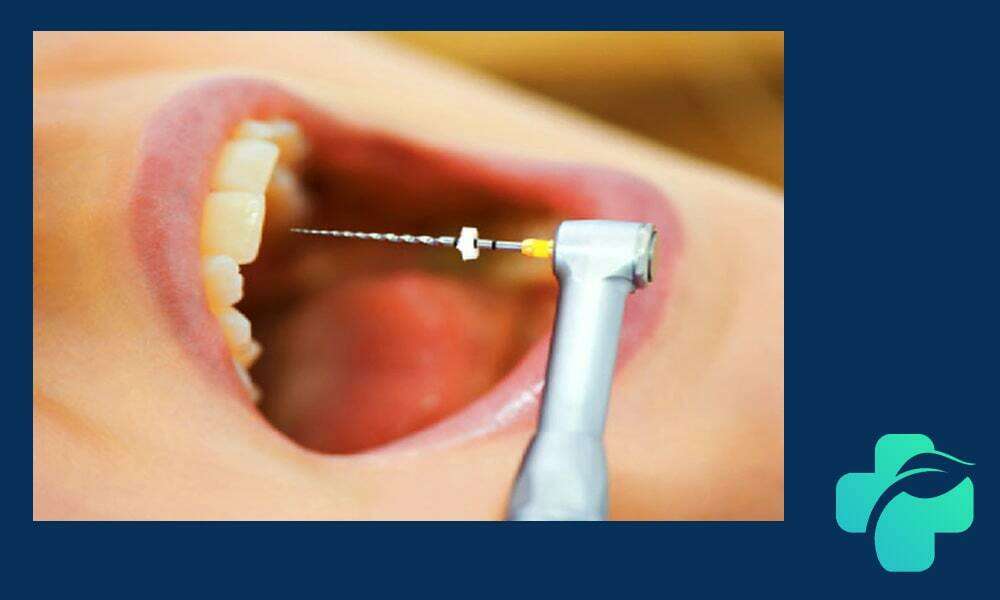

عصب کشی دندان، که به آن درمان کانال ریشه یا روت کانال نیز گفته می شود، یکی از مهم ترین روش های درمانی تخصصی برای حفظ دندان آسیب دیده است. این فرایند با حذف عصب ملتهب یا عفونت کرده داخل دندان، به ترمیم و جلوگیری از کشیدن دندان کمک می کند. در این مقاله، شما را با مراحل عصب کشی دندان، نشانگان نیاز به درمان، انواع روش ها و مراقبت های بعد از عمل آشنا می کنیم تا بتوانید با شناخت بهتر، بهترین تصمیم را در حفظ سلامت دندان های خود بگیرید.

مراحل درمان عصب کشی دندان

درمان ریشه دندان معمولا توسط دندانپزشک متخصص با دقت بالا انجام می شود و شامل چند مرحله اصلی است:

- بی حسی موضعی: برای جلوگیری از درد، ناحیه دندان کاملا بی حس می شود.

- حفر حفره روی دندان: برای دسترسی به پالپ دندان، دندانپزشک با توجه به محل و وسعت آسیب، سوراخی روی دندان ایجاد می کند.

- پاکسازی کانال ریشه: با استفاده از ابزارهای مخصوص، عصب ملتهب یا عفونی تخلیه و کانال های داخلی تمیز می شوند.

- پرکردن کانال ها: پس از پاکسازی کامل، کانال ها با مواد مخصوص پر شده تا از ورود دوباره باکتری ها جلوگیری شود.

- ترمیم نهایی دندان: معمولا پس از عصب کشی، دندان نیازمند ترمیم با پرکردگی یا روکش برای بازگرداندن عملکرد و زیبایی است.

این مراحل با اصول علمی مشابه عصب کشی اطفال انجام می شود، با این تفاوت که در درمان دندان های شیری، از روش ها و مواد ملایم تر برای حفظ ساختار دندان استفاده می شود. رعایت دقیق هر مرحله، موفقیت درمان و جلوگیری از عوارض بعدی را تضمین می کند.